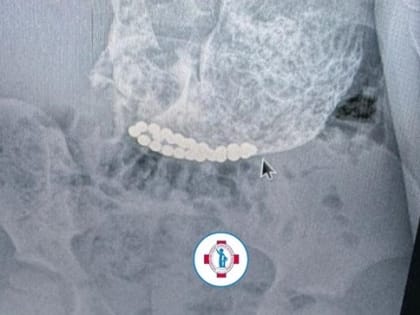

Ставропольские врачи спасли трех проглотивших магнитные шарики детей

За три месяца врачи Ставропольской краевой детской клинической больницы извлекли из организмов трех детей магнитные шарики.

Магнитные шарики из желудка и кишечника извлекли ставропольские врачи у трех детей

Инородные тела в организме могут угрожать не только здоровью, но и жизни Фото: